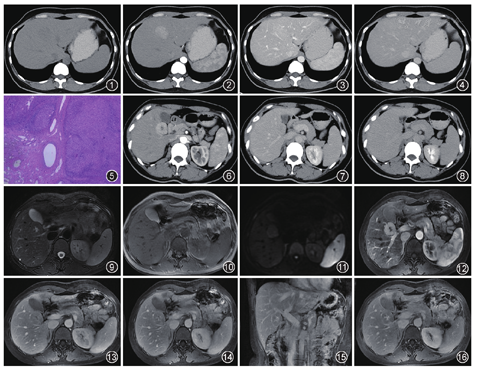

例1女,41岁。病史:体检发现肝脏占位性病变3个月余。实验室检查未见异常改变。影像表现:行CT平扫+增强扫描,平扫肝左内叶见片状略低密度影,密度较均匀,与肝脏分界不清,CT值51.5 HU。增强扫描动脉期,病变明显均匀强化,CT值93.2 HU,边界显示清晰,最大截面35.7 mm×41.1 mm;门静脉期病变较肝实质背景呈略高密度,均匀强化,CT值134.1 HU,边界欠清晰。延迟期病变相对于肝实质背景呈等密度(图1,图2,图3,图4)。病理诊断:肝病变形态符合局灶性结节增生(focal nodular hyperplasia,FNH),切面4.0 cm×2.5 cm,部分肝细胞轻度异型增生,局灶胆管增生,肝组织切缘未见病变(图5)。免疫组织化学:人凝溶胶蛋白(GS)部分阳性,磷脂酰肌醇蛋白多糖-3(GPC-3)阴性,肝细胞石蜡抗原(HepPar-1)阳性,CD34(血管)阳性,Ki-67阳性率2%。特殊染色:网状纤维染色阳性。

例2女,22岁。病史:体检发现肝占位1周。影像表现:腹部CT增强扫描,动脉期病变明显强化,CT值94.1 HU,边界清晰,最大截面28.1 mm×27.6 mm,中心见低密度灶(图6)。门静脉期病变呈略低密度,CT值78.4 HU,边界欠清晰,中心见低密度灶(图7)。延迟期病变呈略低密度,CT值70.24 HU,边界欠清晰,中心低密度灶可见延迟强化(图8)。上腹部MRI平扫+增强扫描,脂肪抑制T2WI,病变呈等信号,中心瘢痕呈高信号(图9);T1WI病变呈等信号,中心瘢痕呈低信号(图10);DWI病变呈略高信号(图11);增强扫描动脉期病变明显强化,中心瘢痕尚未强化(图12);门静脉期病变呈等信号,中心瘢痕尚未强化(图13);增强扫描延迟期病变呈等信号,中心瘢痕出现放射状强化(图14,图15,图16)。